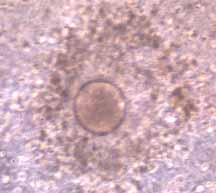

Mature

Human

Egg